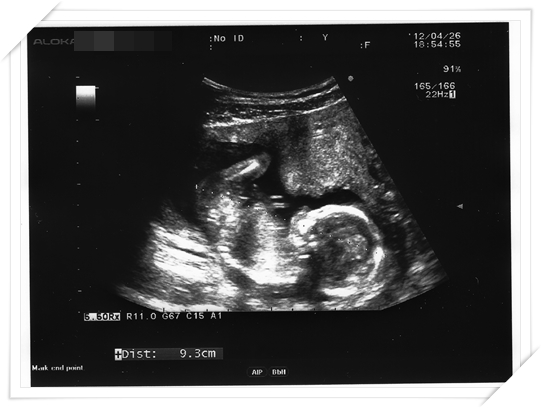

不過 雖然能去產檢很開心 (能看到超音波!)

產檢的時候明明都看到明顯長大很多了

產檢的時候 baby 果然很配合地

一照就照出來啦 一清二楚的 都假不了啦!!!!

所以 我總算總算在15週知道baby 的性別啦!!

第二次其實就是最近這幾個星期的事情 我夢到我去照超音波